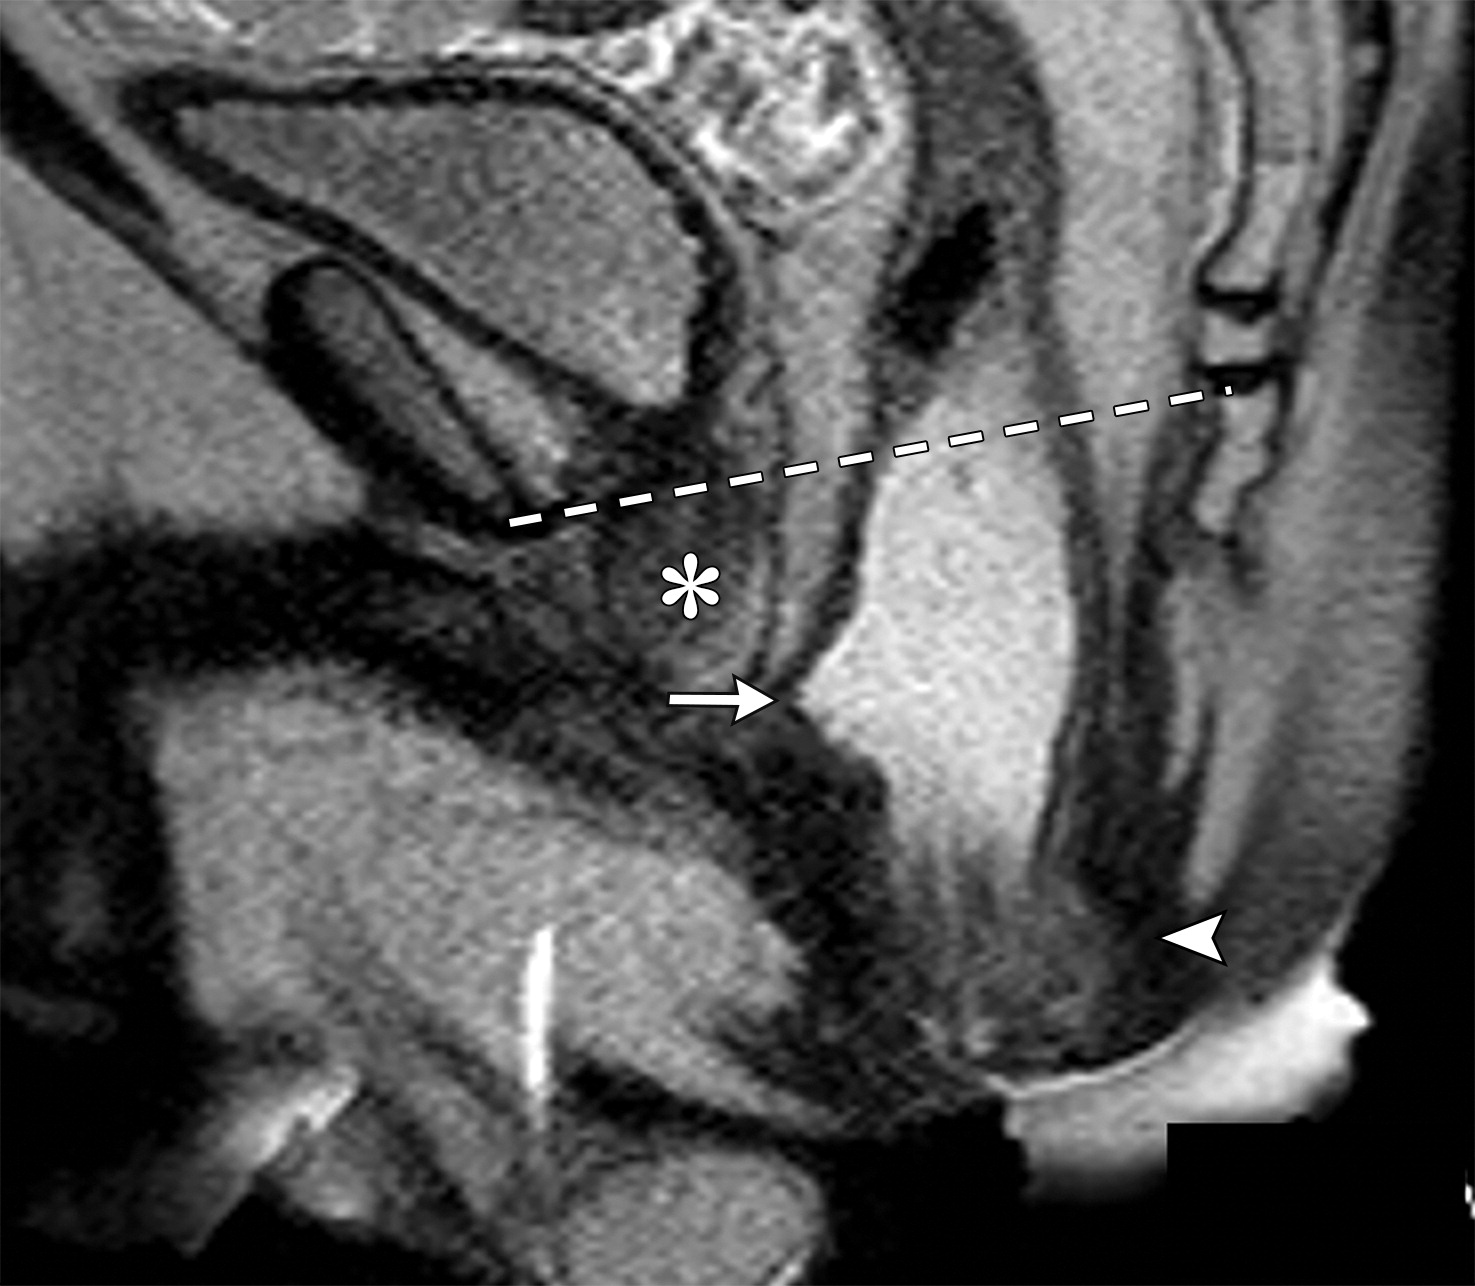

肛门直肠下降及直肠前突。

(a图)为静息态,(b图)为增加腹压态,显示肛门直肠下降(b图中白色短箭头),直肠前突(b图白色长箭头),注意观察前列腺(b图中白色*)位于耻尾线之下(b图中白色虚线)。